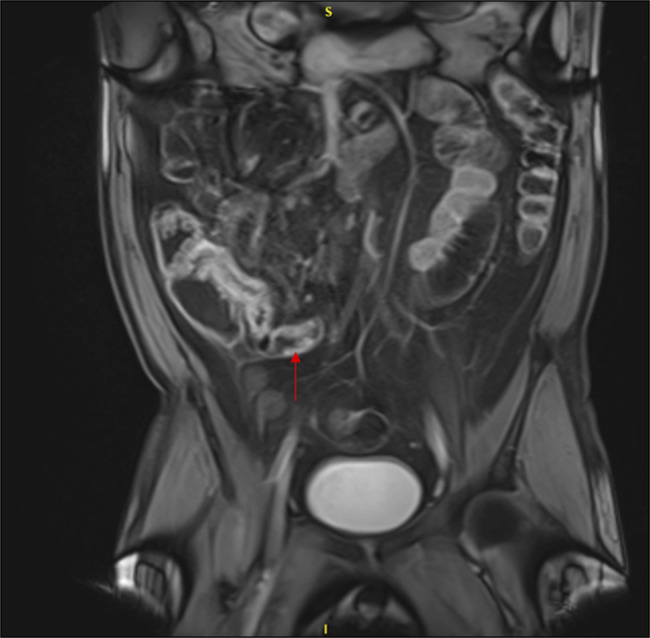

肉芽肿病合并多血管炎(GPA)是一种罕见的小血管炎,通常表现为多器官累及上呼吸道、肺和肾脏。我们报告一位55岁的男性,他表现为口腔溃疡疼痛,弥漫性关节疼痛,鼻出血和间歇性的栗色大便。传染性评价无显著差异。风湿病学评估显示c-抗中性粒细胞细胞质抗体和蛋白酶3抗体升高。结肠镜检查与回肠末端活检显示血管中心炎性发现支持GPA的诊断。本病例的临床表现不同寻常,以口腔表现为主。对于胃肠道出血的患者,GPA的诊断仍然需要鉴别,这些全身性症状需要高度的怀疑才能及时诊断。

Granulomatosis with polyangiitis (GPA) is a rare small vessel vasculitis that commonly presents with multiorgan involvement of the upper airways, lungs, and kidneys. We report a 55 year-old-man who presented with painful oral ulcers, diffuse joint pain, epistaxis, and intermittent maroon bowel movements. Infectious evaluation was unremarkable. Rheumatologic evaluation demonstrated elevated c-anti-neutrophil cytoplasmic antibody and proteinase 3 antibodies. Colonoscopy with terminal ileum biopsies demonstrated angiocentric inflammatory findings supportive of a diagnosis of GPA. This case was unusual in its presentation with predominately oral manifestations. A diagnosis of GPA should remain on the differential for patients with gastrointestinal bleeding, and these systemic symptoms require a high level of suspicion to lead to timely diagnosis.